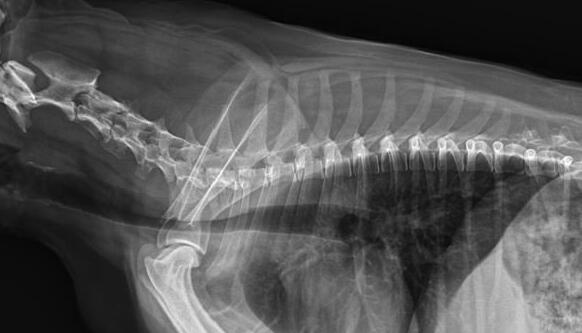

利用寵物dr拍攝圖像效果圖

1、DR的DQE檢測(cè)效率可達(dá)74%,而傳統(tǒng)普通膠片組合X線照片DQE為30%。

2、寵物DR成像速度快,采集時(shí)間10ms以下,成像時(shí)間僅為3秒,對(duì)于受傷的寵物來說,檢查越快速,越能早點(diǎn)幫助其治療,降低痛疼。對(duì)于寵物主人而言,也是一種心理安慰。

3、數(shù)字圖像可進(jìn)行后處理。圖像后處理是數(shù)字圖像的很大特點(diǎn)。只后要保留原始數(shù)據(jù),就可以根據(jù)診斷需要,并通過軟件功能,有針對(duì)性的對(duì)圖像進(jìn)行處理,以提高診斷率。

4、獸用dr所具備的輻射劑量較低,相比傳統(tǒng)的ct而言,對(duì)于寵物和醫(yī)生而言,都是一種保護(hù)。

5、有效解決了圖像的存檔管理與傳輸,采用光盤刻錄形式保存圖像資料,隨時(shí)能為受檢者提供照片打印服務(wù),這樣大大提高了工作效率。對(duì)于接診量比較大的寵物醫(yī)院來說,這個(gè)具備大的優(yōu)勢(shì)。